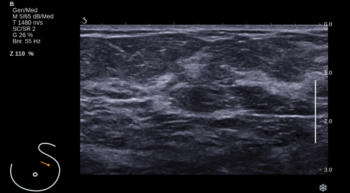

Figure 1. Images in a 55-year-old screening participant. (a, b) Normal digital full-field mediolateral oblique (a) and craniocaudal (b) mammograms (BI-RADS category 1) show a heterogeneously dense breast (ACR category C). (c) Screening ultrasound image shows normal findings (BI-RADS category 1). (d) MR-guided biopsy enabled us to confirm the presence of an invasive high-grade triple-negative cancer (no special type [NST], pT1b, N0, M0). (d) Breast MR image shows a suspicious enhancing mass (arrow) in the left breast (BI-RADS category 5).E

Figure 5. Screening ultrasound image shows normal findings (BI-RADS category 1).